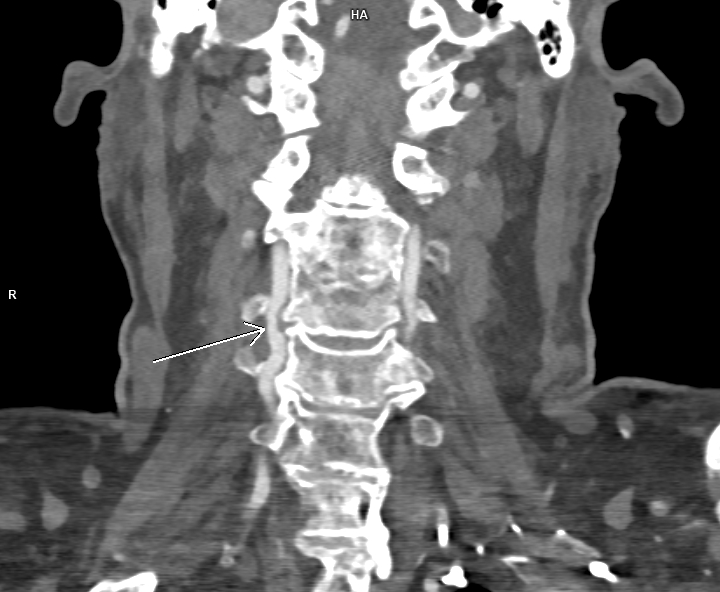

Figura 2: reconstrucție coronală din achiziție angioCT trunchiuri supraaortice

Discuţie caz nr 116: Pe imaginile prezentate se observă reducere de calibru de 60-70% a arterei vertebrale drepte datorată compresiei extrinseci de către o hernie de disc extraforaminală. Leziunile severe de artere vertebrale, mai ales la pacienții tineri care nu au dezvoltat colaterale, produc leziuni cerebrale de fosă posterioare și / sau ganglioni bazali. La acești pacienți se recomandă angioCT sau, unde este posibil și există expertiză, angioRM de trunchiuri supraaortice pentru suspiciune de disecție de perete vascular.